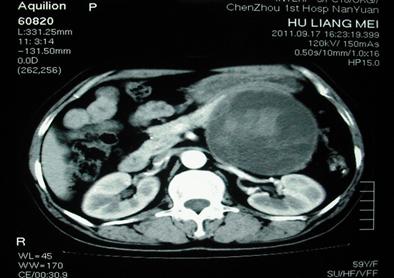

这就比前一种要严重一些了,又称大囊性囊腺瘤或癌(macrocystic adenoma/adenocarcinoma),其中大部分的病例仍为女性,也好发于胰腺尾部,典型者由一个或多个大囊组成,其囊壁薄厚不均伴强化(<1cm),囊壁分隔菲薄呈线状,可伴钙化,液体成分密度不均(由于内部出血或液体中蛋白浓度差异所致)

粘液性囊腺瘤要比浆液性囊腺瘤严重

肿瘤的大小与恶性程度相关,直径>8cm则考虑恶性可能大;若发现囊壁有结节状改变、不规则厚壁、突入腔内的壁结节并有强化实性成分,那么就应考虑为囊腺癌,病理以伴有卵巢样间质(ovarian-like stroma)为特征。由于粘性性囊腺瘤更容易恶变,所以手术就应更为积极。